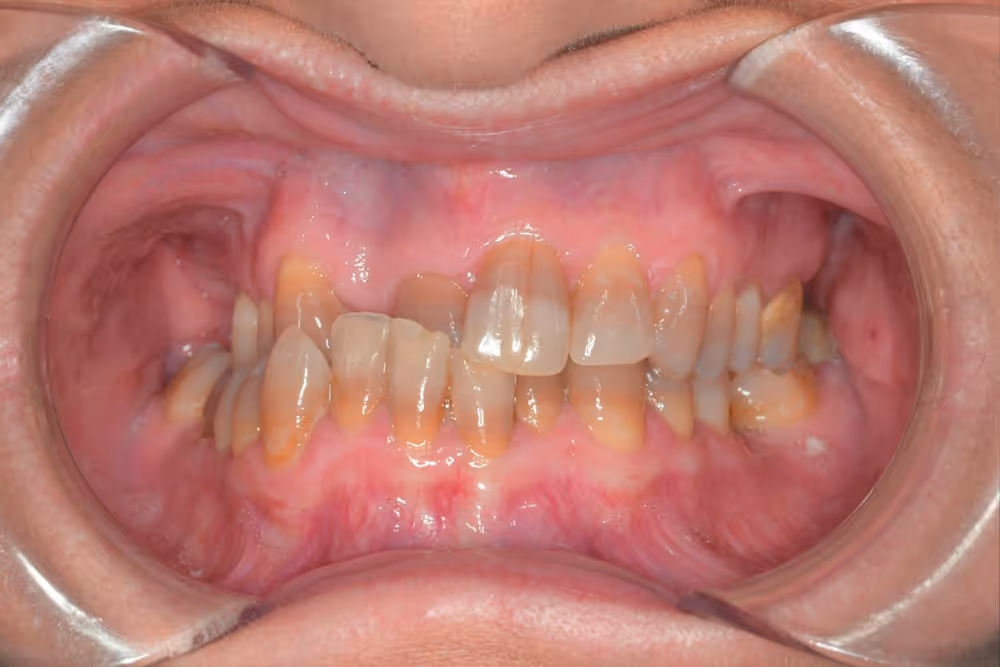

Existen determinados casos en los que la diferencia entre la posición de los maxilares (maxilar superior y mandíbula) es tan grande que un tratamiento de ortodoncia convencional no será suficiente para corregir la mordida.

Te invitamos a conocer algunos de nuestros casos clínicos, donde podrás comprobar de primera mano la transformación que podemos lograr gracias a un enfoque multidisciplinar y a la excelencia que aplicamos en cada paciente.

En cada uno de estos casos, la especialización en las diferentes áreas de la odontología, el trabajo en equipo y la atención individualizada han sido claves para conseguir resultados óptimos.